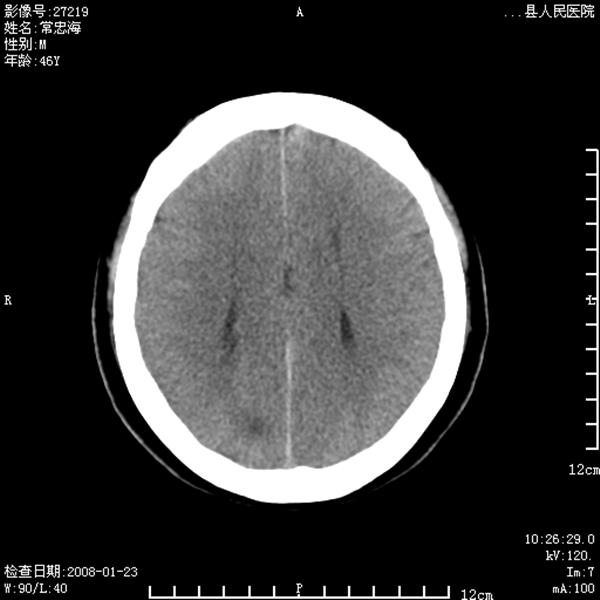

以下是引用江边学者在2008-4-19 22:26:00的发言:[br]1.胼胝体发育不良。[br]2.右侧眼球痨。[br]3.右侧颜面部软组织挫伤。